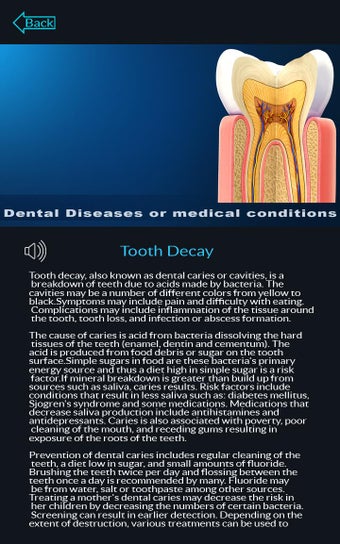

Esta aplicación es un modelo 3D de los dientes, que contiene muchas partes y muestra las condiciones dentales. Cada parte tiene un nombre y una función. Puedes mover la cámara alrededor del modelo para obtener una vista de 360° de las diferentes partes. Puedes hacer zoom para ver mejor cada parte. También puedes rotar la cámara para obtener una vista diferente del modelo.